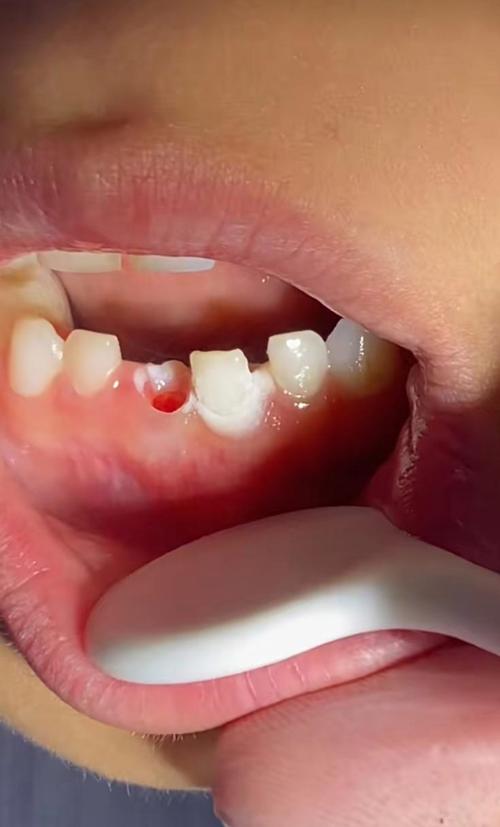

Q1:正畸过程中牙齿松动是正常的吗?会不会脱落?

A:正畸中牙齿轻微松动(Ⅰ度松动,动度<1mm)是生理反应,因牙周膜在压力下改建,属于“可控范围内的暂时状态”,若出现Ⅱ度松动(动度1-2mm)伴咬合痛、牙龈溢脓,或牙齿“浮起感”明显,需警惕牙根吸收或牙周炎,需立即复诊拍摄根尖片及牙周检查,及时调整治疗方案,脱落风险极低,仅见于未控制的严重牙周炎或牙根吸收超过根长2/3的情况。